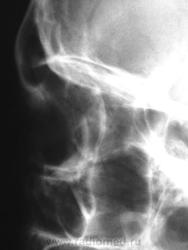

Стрелки не очень видны, но может это здесь?

Ощущение что это образование на боковой проекции определяется в переднечерепной ямке, интимно лежащая на кости.

К малому крылу прилепилась остеомка или менингиомка.

А покрутить на скопии не пробовали? Или сделать УЗИ глазного яблока. Возможно это не в костях, хотя сильно смахивает на остеому.

Соглашусь с коллегами по локализации очага. Но вот явная слоистость не подходит для остеомы. Наверное, менингиома с обызвествлением.

Наверное, менингиома с обызвествлением. Кроме этого ничего не придумал).

Добавил увеличенный фрагмент бокового.